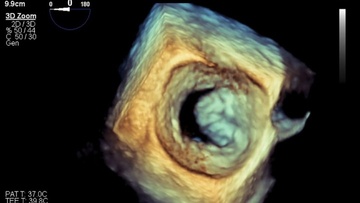

Αμιγώς διαδερμική αντικατάσταση μιτροειδούς βαλβίδας μέσω της μηριαίας φλέβας πραγματοποιήθηκε για πρώτη φορά παγκοσμίως σε δύο ασθενείς με σοβαρή καρδιακή ανεπάρκεια, στο Ιατρικό Διαβαλκανικό, από τον διευθυντή της Β’ Καρδιολογικής Κλινικής, επεμβατικό καρδιολόγο Βλάση Νινιό και την ομάδα του.

Έχουμε τη δυνατότητα ν’ αντικαταστήσουμε τη μιτροειδή βαλβίδα που έχει ανεπάρκεια, τοποθετώντας μία νέα, σε συγκεκριμένη θέση μέσα στην καρδιά.

Η βαλβίδα αυτή (AltaValve), είναι η πρώτη του είδους της που εμφυτεύεται με το καινούργιο σύστημα της αμερικανικής εταιρείας 4C MEDICAL η οποία επέλεξε τον κ. Νινιό και το Διαβαλκανικό για την εφαρμογή του.